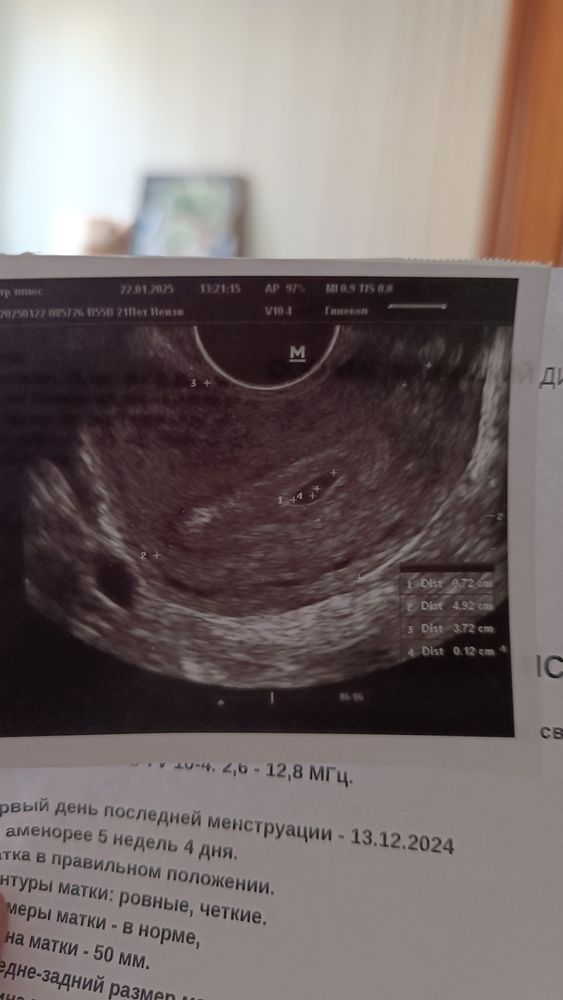

Всё хорошо. Мы подросли, срок 4 н и 2д от зачатия. По аменорее 5 н и 6 д.( узист посчитала не верно. Поставила 5 н и 4 дня)

Плодное яйцо 7мм.

Желточный мешочек 1,3. Малыша пока не видно.